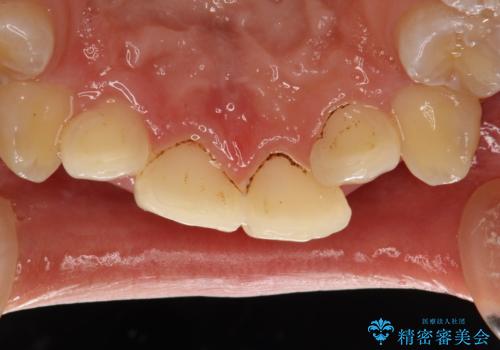

- 矯正治療前にステインを取りたいとのことで来院されました。ステインは前歯のみだったため、PMTC30分コースを行いました。

PMTCとは、歯科の専門家が器械を使用して行う歯のクリーニングのことです。普段の歯磨きでは取り切れない溝、キワなどの細かい部分も徹底的に除去します。ステインや歯石などが付着したままだと、虫歯や歯周病の発見がしずらいことがあります。特に矯正治療前には、念入りな虫歯や歯周病チェックが必要なため、PMTCでしっかりと汚れを除去しておくことが大切です。